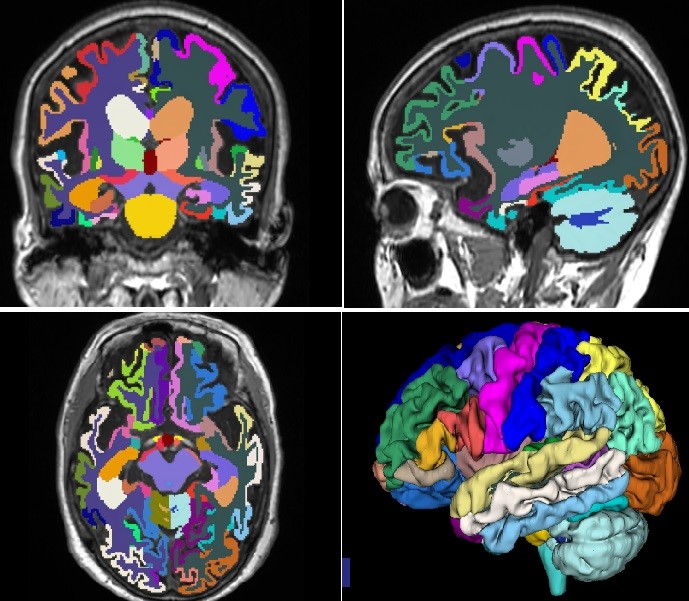

人工智能脑分割技术